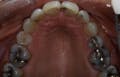

You know the old saying, “A picture is worth a thousand words.” Think about that saying and what it means. It’s basically saying that you paint a visual image that does not need to be described by words. Now look at this photo and think of all the words coming to your mind. (Image 1.1, left) Infection? Broken? Missing? Holes? Is this what patients might be thinking if this were a photo of their mouth? This doesn’t need to be described by the dentist, hygienist, or the dental assistant. Digital photos take you 1,000 words deeper into conversations with your patients. What happens is that when you place the photos on the monitor and scroll through them, patients ask questions. Also, patients instantly believe that what you are about to discuss is real. Why? Because they can see it with their own eyes. This removes the emotional wall often experienced by patients when it comes to dental care. You know the one I’m talking about — “Oh, they’re trying to sell me something.” If you have not yet incorporated this armamentarium into your practice, you are ultimately losing opportunities to connect with your patients and discuss whole mouth dentistry, elective care, and even basic health needs. Whether you have a moderately priced, high-end intraoral, or digital still camera, you and your team should take time to integrate it into your daily routine. Make it a habit to capture digital camera images like you do X-rays.